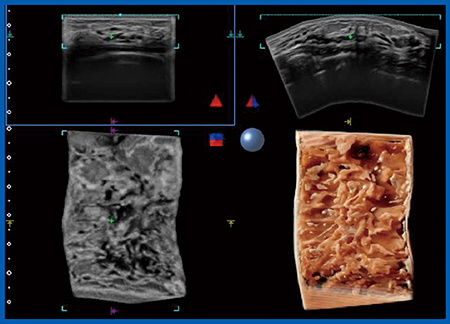

Aplio iシリーズには,新しい機能として,フリーハンドでスキャンした範囲の情報をつなげて立体的に画像を再構築する技術“Smart Sensor 3D”が搭載された。これまでも4Dプローブを用いて限られた範囲の3D画像を再構成することはできたが,24MHzのPLI-2004BXにより,高周波リニアプローブで3D画像を得ることができるようになった。Smart Sensor 3Dではスキャンデータをボクセルデータとして保存して,冠状断や頭尾方向の3D画像を再構成し,皮膚を透かして見るように,コントラストが異なる部分が浮き立ったShadow Glass画像を観察することができる(図12 右下)。再構成した画像は,光源の位置を変えたり回転したりするなど,任意に観察が可能である。検査をしながらその場で再構成画像を表示できるため,3D画像を回転して腫瘤の範囲を確認するなど,活用範囲が広がるかもしれない。

図12 Shadow Glass画像(右下)